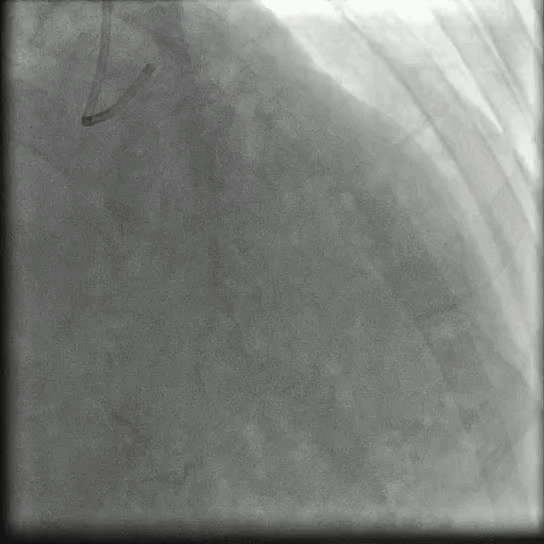

心臟檢查方式四:冠脈造影

“此項(xiàng)目能檢查房間里的水管堵沒(méi)堵,因?yàn)楣茏佣际氰F皮包著,里邊銹成啥樣造影就能看見(jiàn)。”

冠狀動(dòng)脈造影是目前診斷冠心病最直接、最可靠的方法。對(duì)于其他無(wú)創(chuàng)檢查方法都不能確診的患者,冠脈造影檢查是唯一一種可提供有力診斷依據(jù)的手段。推薦閱讀: